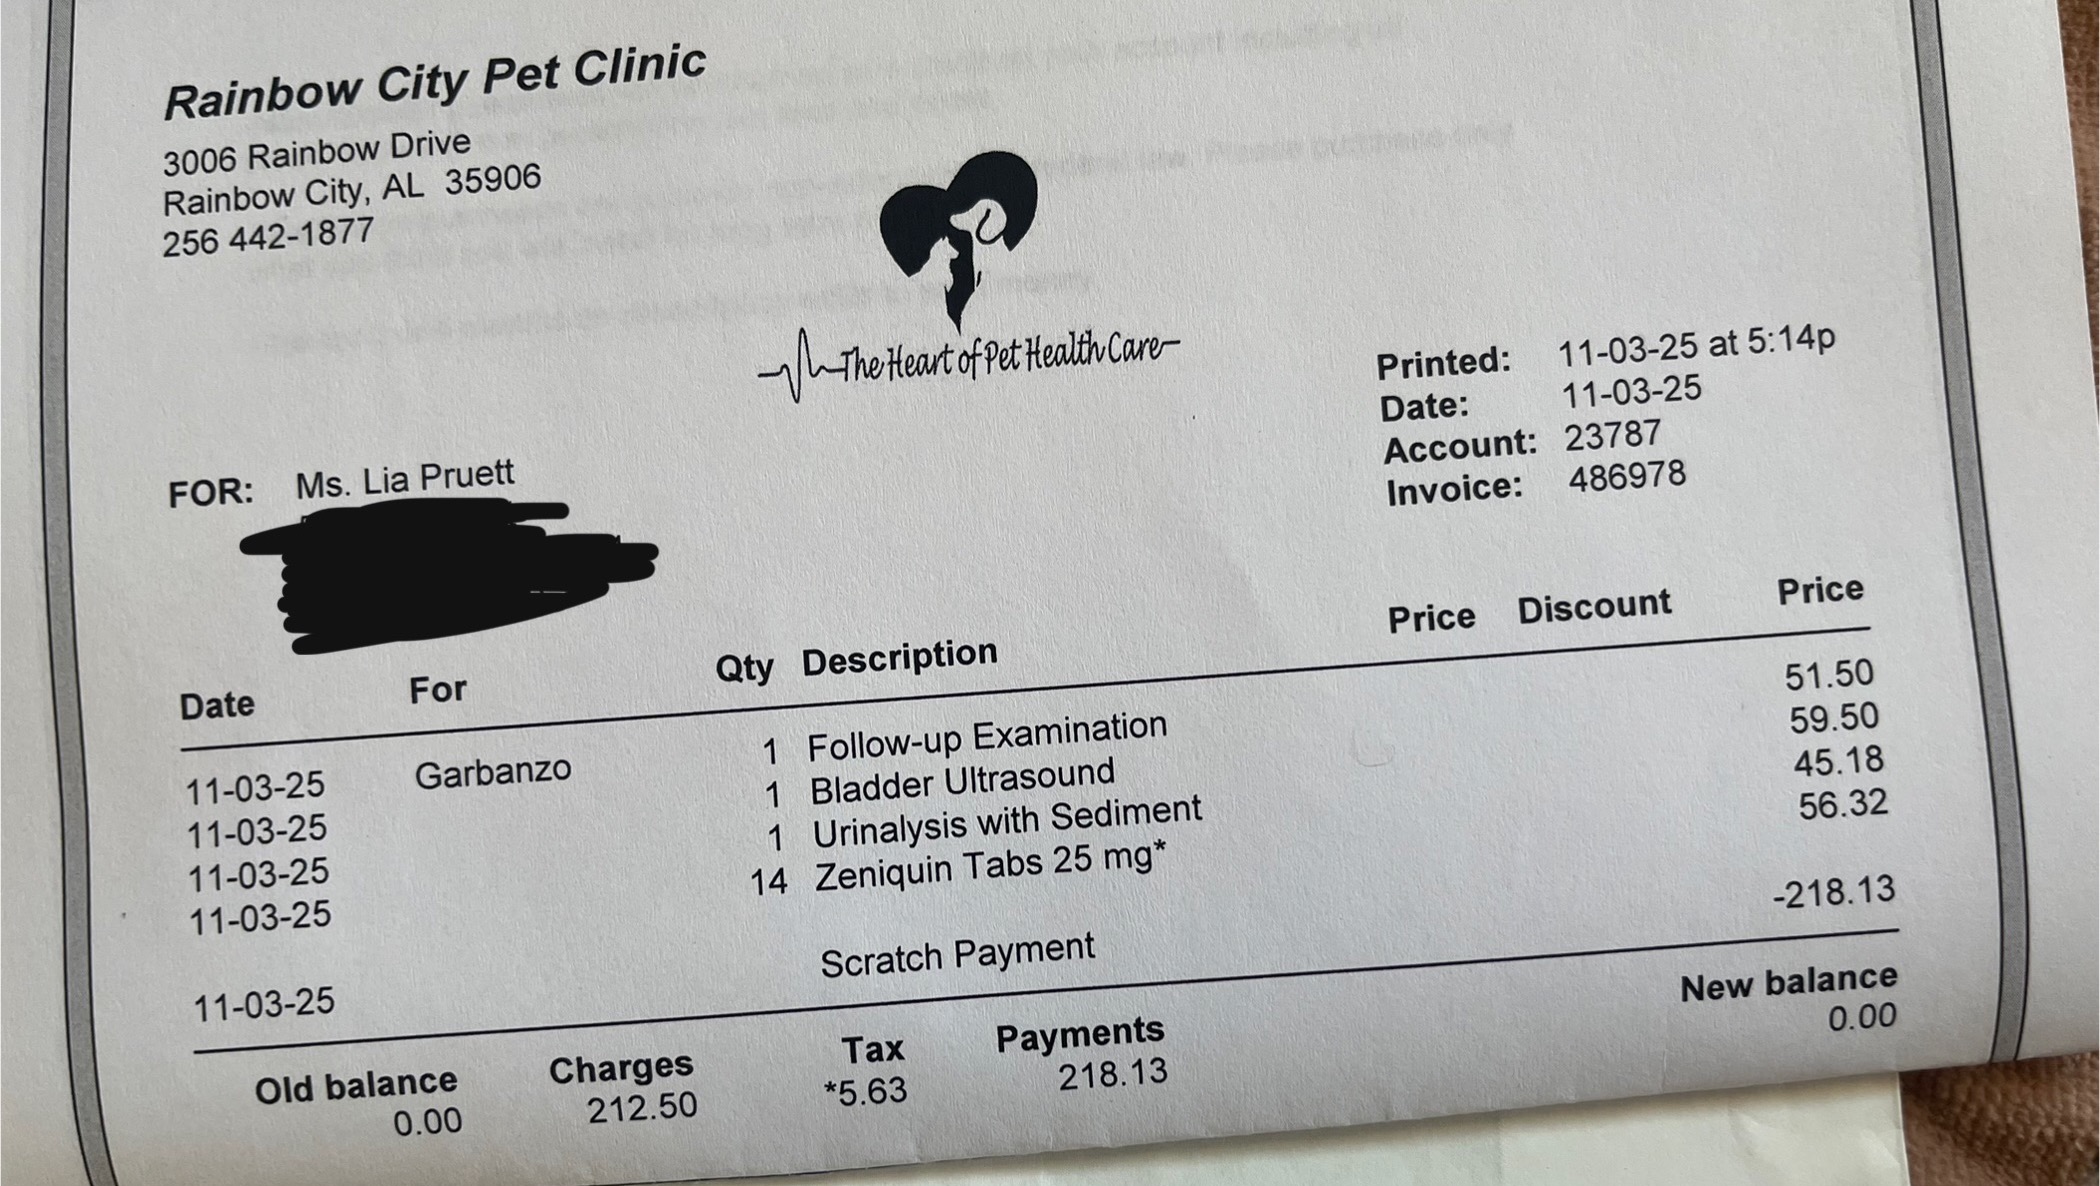

In late September, Garbo had to stay at Rainbow City Pet Clinic for five days due to a blocked urinary tract. The treatment cost almost $1,200, and though CareCredit helped cover most of it, we've continued to face escalating vet bills. Since then, Garbo has needed additional visits—2-3 more since his stay—making this situation more financially draining than we could have ever anticipated.

On Monday, November 3rd, Garbo went back to the vet. They discovered three stones in his bladder but assured us there was no immediate blockage. They prescribed antibiotics in hopes of them breaking them up on his own.

But by Wednesday, November 5th, Garbo's condition deteriorated drastically. He wasn’t moving, eating, or drinking. He seemed so weak and lethargic, it was heartbreaking to watch. I rushed him to the emergency vet at 2 a.m., and after a $300 emergency treatment, they drained his bladder, which was filled with bloodied urine. He was blocked.

As I write this, Garbo is still at the vet, and his bills are adding up fast—another $1,000 on top of everything else. That much was paid out of our own pockets.

Any donation, no matter how small, will go directly toward his treatment and surgery. We'll provide proof of payment for all vet bills and CareCredit charges, so you can see exactly where your donation is going.